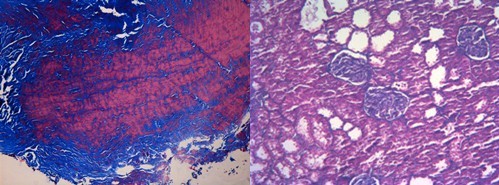

Masson染色法是利用两种或三种阴离子染料混合或先或后作用完整鉴别染色的。胶原纤维呈蓝色,肌纤维呈红色。 实验步骤:

7. 无水乙醇脱水,二甲苯透明,中性树胶封片结果为胶原纤维呈绿色,肌纤维呈红色,红细胞呈橘红色

结果示意图: